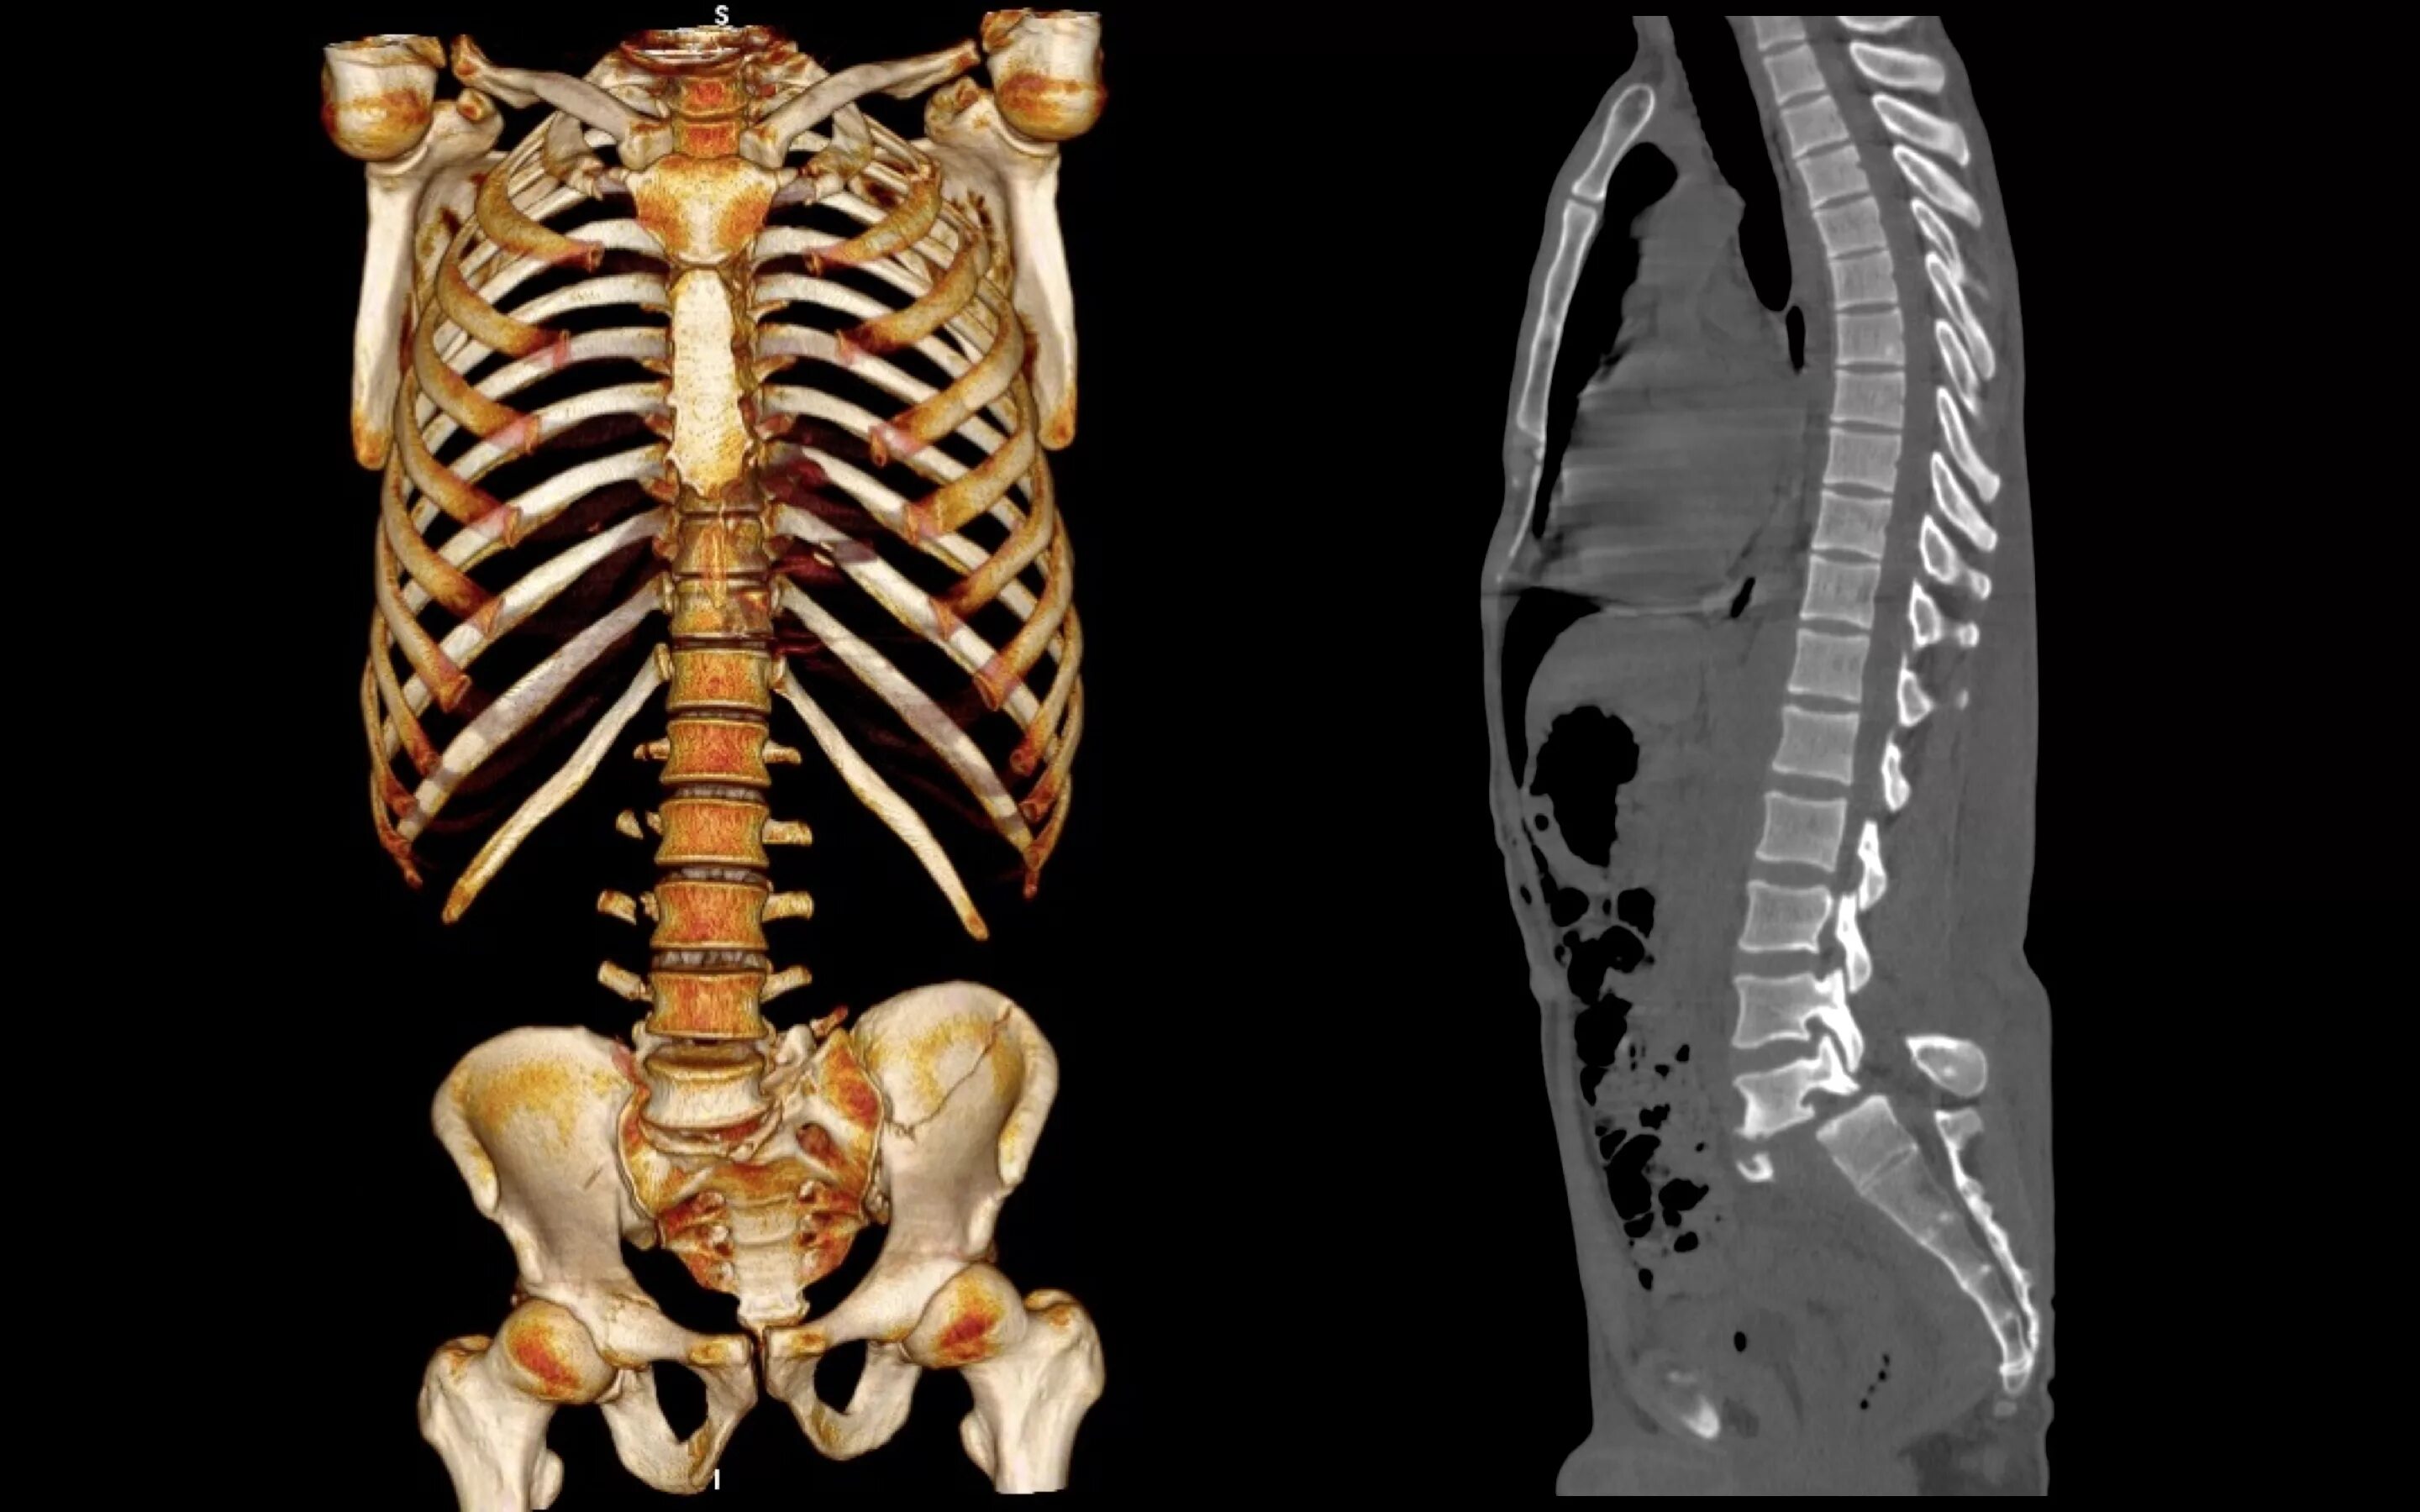

Пояснично крестцово копчиковый отдел